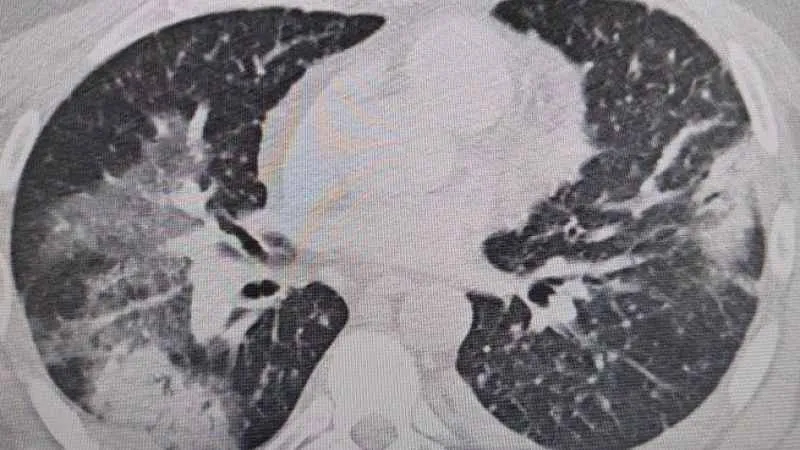

Prof. Dr. Şevket Özkaya, “Legionella” bakterisinin klima sularında üremesiyle insanların yaz zatürresine yakalandıklarını ve kış aylarına göre çok daha fazla vakayla karşılaştıkları bilgisini verdi. Klima zatürresinin özellikle kronik rahatsızlığı olanlarda ölümcül olabileceğini belirten Prof. Dr. Şevket Özkaya önemli uyarılarda bulundu. Özkaya, “Klimaların havalandırılmasıyla beraber insanlar 'lejyoner' bakterilerini akciğerlerine aldığında 'klima pnömonisi' ya da 'yaz zatürresi' dediğimiz hastalığa yakalanıyorlar. Bunun özellikle kronik astım, KOAH ve kanser hastalarında ölümcül sonuçlar doğurabileceğini biliyoruz” dedi.